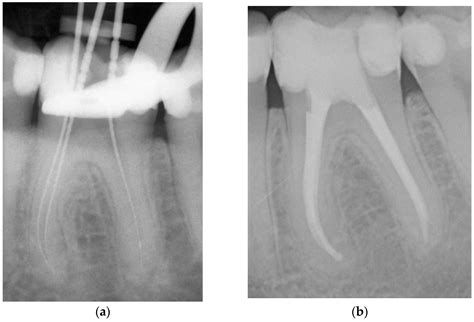

1. Diagnosis and Anesthesia: Your dentist will take X-rays to assess the extent of the infection. Local anesthesia is administered to ensure you do not feel pain during the treatment.

3. Cleaning and Shaping: The infected pulp is carefully removed using specialized dental instruments. The canals are then cleaned, disinfected, and shaped to receive a filling material.

4. Filling and Sealing: The hollowed-out canals are filled with a biocompatible material called gutta-percha, which is cemented into place.